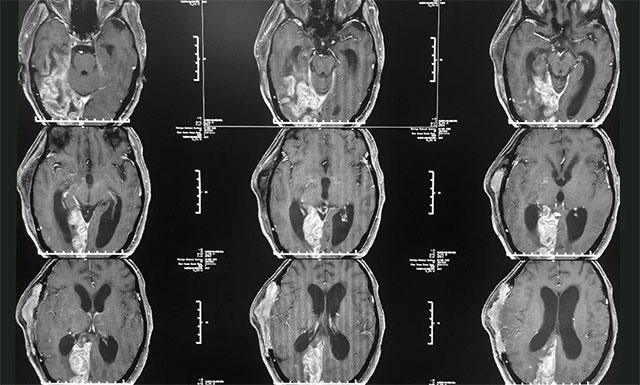

患者葛女士颅内重度感染,情况不容乐观,对此吴治群博士介绍说:“患者因其之前脑脓肿比较严重,术后又出现了一系列并发症,颅内严重感染,伴颅内高压,脑积水也非常严重;来院时患者就陷入了深度昏迷,当时她的拉斯哥昏迷评分(GCS)仅有6分(GCS评分最高为15分,分数越低则意识障碍越严重);又因之前行去骨瓣减压术,患者右侧颞顶骨大块缺损,脑组织凹陷,脑室受压变窄,情况危急,并收治于6B神经外科监护病房”。

▲ 患者颅内感染严重,情况非常危急

完善各项检查后,潘主任和吴主任针对其病情进行了会诊,一致认为患者目前颅内感染严重,并引发了脑积水,需要及时手术,否则会破坏大脑功能,严重时则可能形成脑疝,甚至昏迷及死亡。随后,潘主任医生团队制定了完善周密的治疗方案。